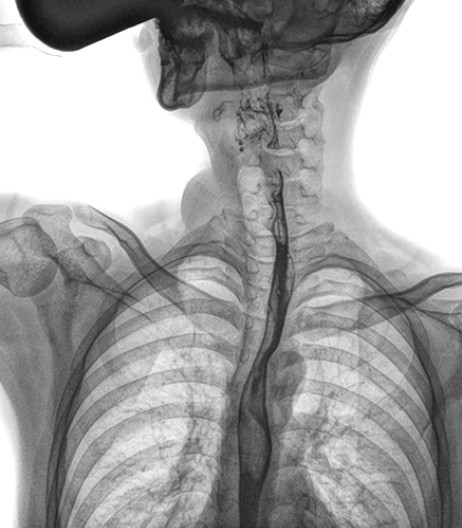

上消化道造影高清圖像

食管造影是食管病變的基本檢查方法,可以發(fā)現(xiàn)食管癌的特征性改變——食管粘膜的中斷和破壞,病人常感覺吞咽障礙,此特征在臨床中最常見,也是早期食管癌的典型表現(xiàn)。一般伴隨的特征有管壁充盈缺損、龕影、軟組織塊影、食管腔狹窄等;在透視下還可看到食管壁僵硬、蠕動緩慢等。

動態(tài)DR能夠?qū)崿F(xiàn)大幅面透視,瞬時(shí)高清點(diǎn)片等。在食管造影檢查中,由于吞咽鋇劑后,造影劑流速非??欤谝粋€(gè)大幅面上方便觀察食管的病變。瞬時(shí)點(diǎn)片,可以實(shí)時(shí)捕捉到病變部位的影像,從而可以快速做出診斷。普利德多功能動態(tài)DR擁有17×17英寸超大視野,一次曝光即可顯示整個(gè)食管,更方便觀察食管的病變,確定病變的范圍,對診斷和治療有重要參考價(jià)值。

與過去的數(shù)字胃腸機(jī)比較,動態(tài)DR圖像分辨率高,對食管的全景觀察,局部粘膜破壞、中斷,管腔狹窄以及病灶范圍的顯示清晰度明顯更優(yōu)。